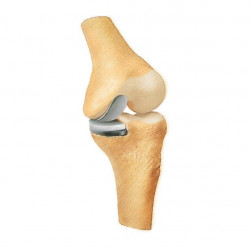

Oberflächenersatz („Knie-TEP“)

Bei einem Verschleiß der gesamten Knorpelfläche bei noch intakten Seitenbändern empfehlen wir einen Oberflächenersatz.

Hierbei werden nur wenigen Millimeter vom Knorpel entfernt um das Implantat passgenau aufzubringen.

Um eine noch höhere Präzision und die bestmögliche individuelle Anpassung des Implantates zu gewähren, bieten wir die Möglichkeit einer individuellen Schnittblockplanung vor der Operation an (Nähere Auskünfte erhalten Sie in der Spezialsprechstunde von Dr. med. Michael Matzer).

Bei einer starken Fehlstellung und stark gelockerten Seitenbändern des Kniegelenkes muss die Stabilität durch ein Implantat mit Schaftverankerung übernommen werden.